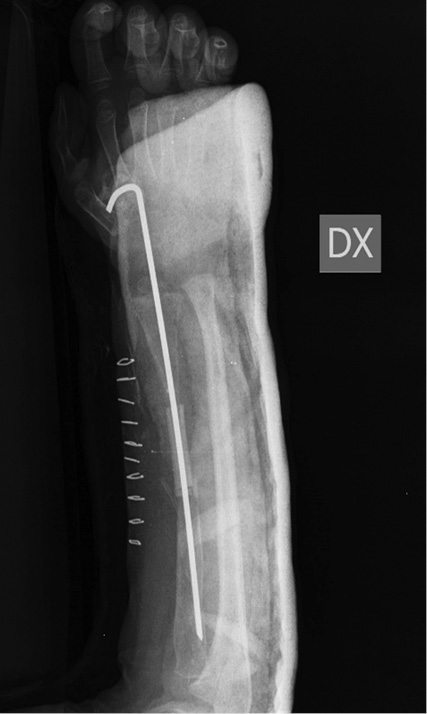

Была выполнена биопсия кости, и по заключению двух разных итальянских центров синдром Горхема – Стоута был исключен, так как выявлены реактивная костная ткань с аномальной васкуляризацией, некротические костно-хрящевые фрагменты и гигантские мононуклеарные клетки. Несмотря на то что пациент поступил в нашу больницу с этими результатами, было решено повторить биопсию, и исключение синдрома Горхема – Стоута было подтверждено. После этого провели дополнительные лабораторные исследования и консультации с большим количеством специалистов, чтобы исключить все причины, которые могли привести к обширному остеолизу. Спустя 11 мес. после последней травмы произведена новая операция на месте перелома с иссечением ткани и имплантированием аутологичного трансплантата малоберцовой кости с факторами роста костного мозга. Трансплантат стабилизирован спицами Киршнера (рис. 4).

Рис. 4. Рентгенограмма до и после иссечения ткани, аутологичная малоберцовая кость с костномозговыми факторами роста, аутотрансплантат стабилизирован интрамедуллярной спицей Киршнера